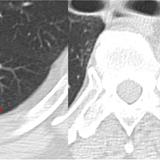

Rounded atelectasis case 1 CT